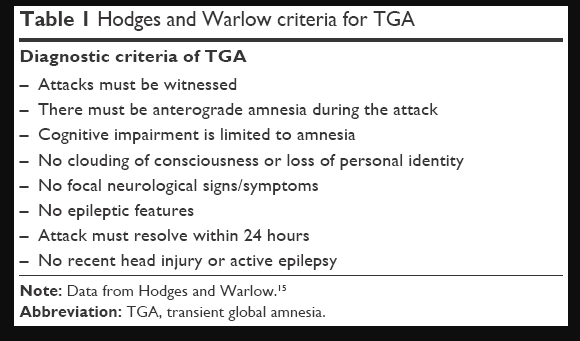

To better help apply the information in this wiki to A-Level studies, two different amnesia disorders will be referred to for examples on each of the key pages. These are: Wernicke-Korsakoff Syndrome (WKS) and Transient Global Amnesia (TGA). Other disorders may be referenced throughout but the three mentioned above will be the focus.